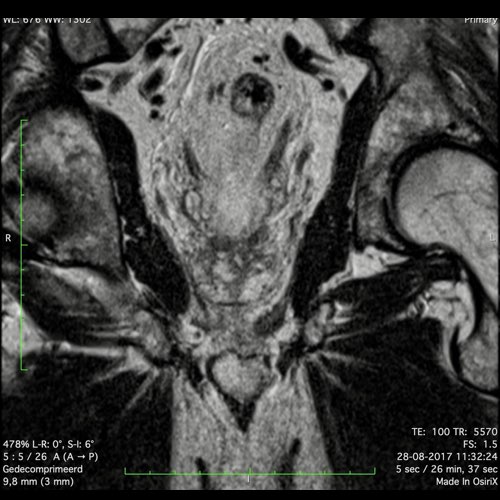

Hình ảnh

Các hình ảnh được cung cấp cho thấy ung thư biểu mô tế bào nhẫn với tình trạng dày lan tỏa thành trực tràng, hình ảnh bia bắn điển hình, và sự xâm lấn mỡ mạc treo trực tràng.